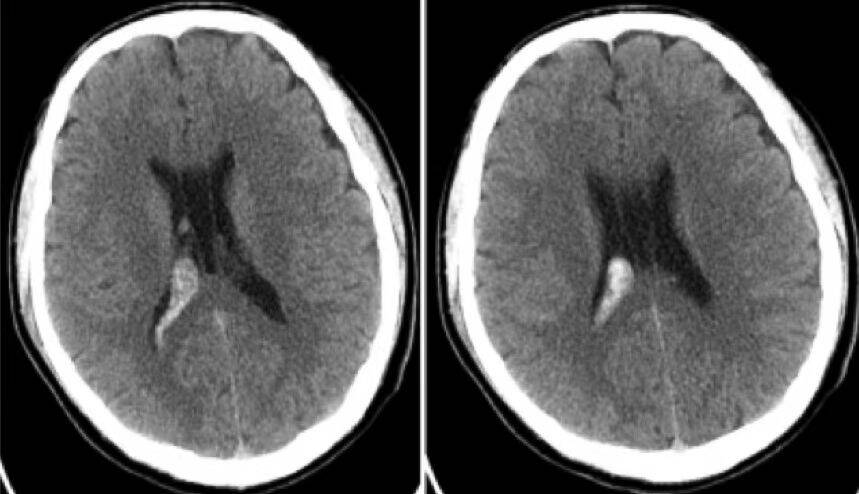

头CT(2014-12-29):见右侧侧脑室出血,可见第5、6脑室。